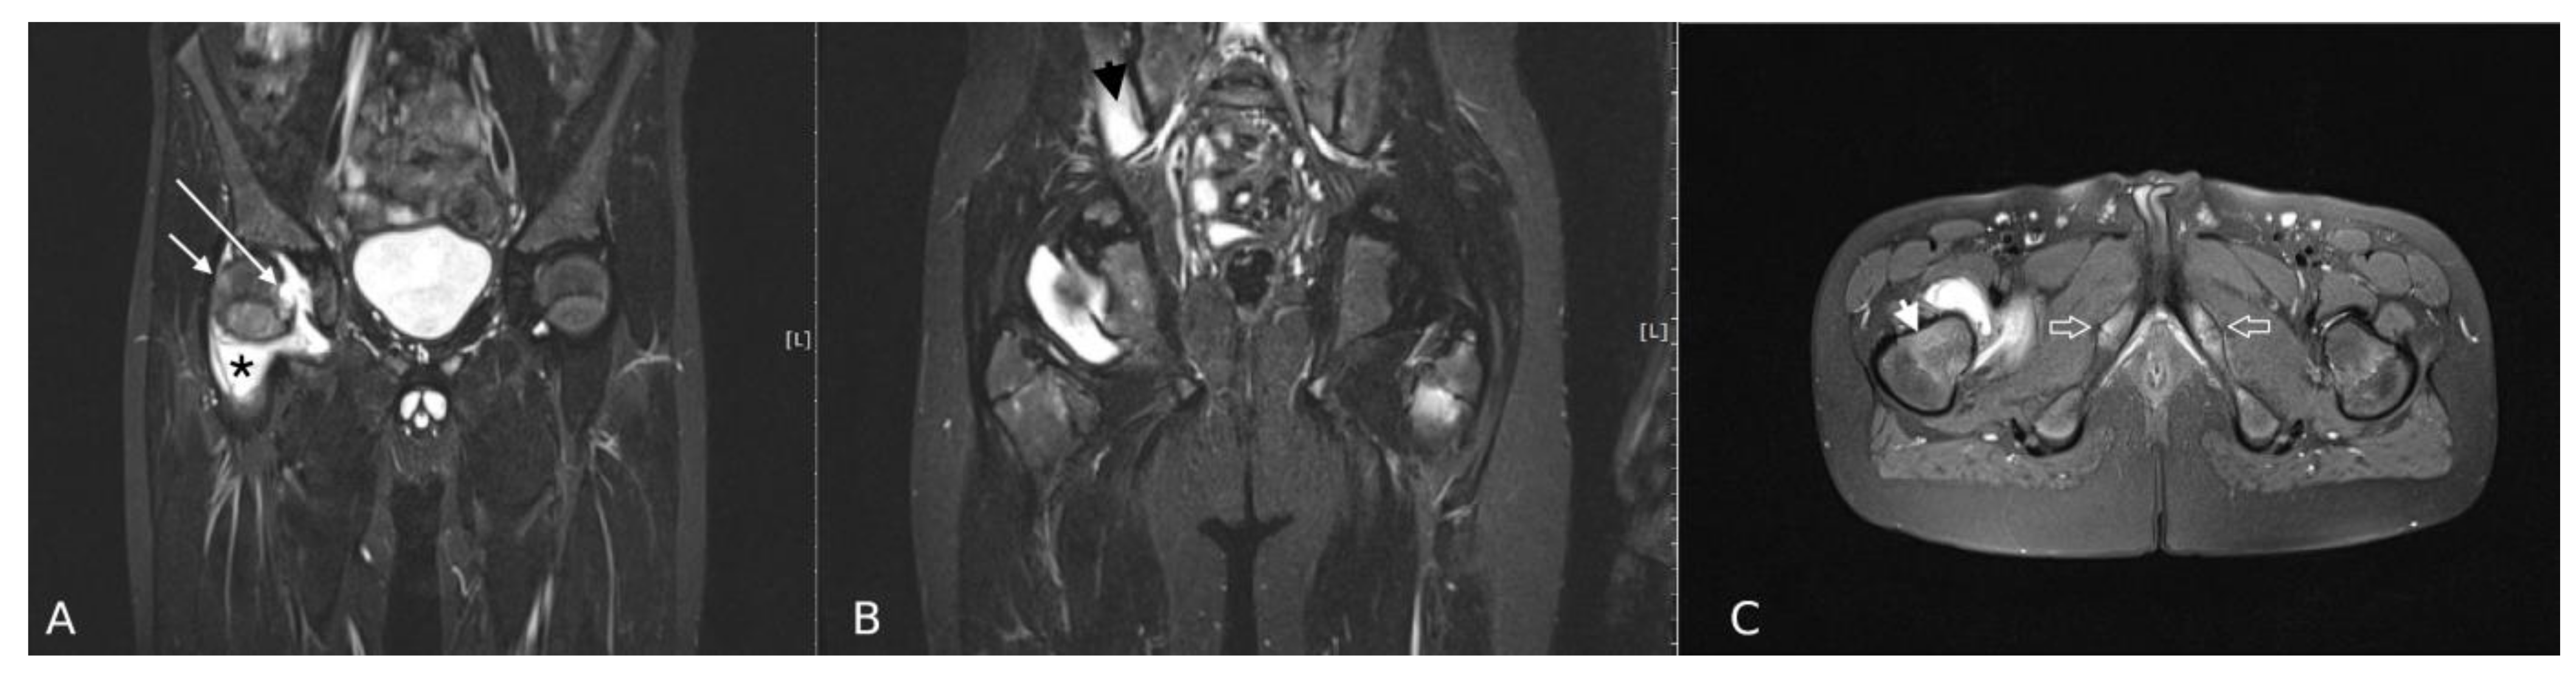

3. Results